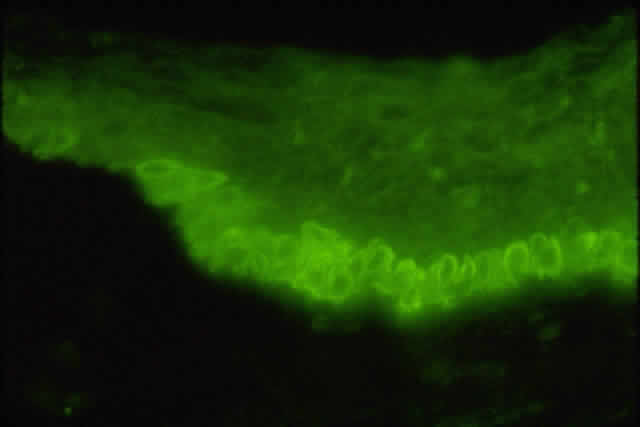

Fig. 15. Immunolocalization of vasoactive intestinal peptide in conjunctival flat mount. Fluorescence micrographs are a montage of sections imaged parallel to the conjunctival surface at 1-μm intervals with a confocal microscope. Vasoactive intestinal peptide-containing nerves appear as green lines.

Fig. 16. Fluorescence micrograph of section from inferior conjunctiva showing tyrosine hydroxylase (TH)-containing nerve fibers. Presence of TH indicates that sympathetic nerve fibers surround individual goblet cells. (Original magnification; × 600. Dartt DA, McCarthy DM, Mercer HJ et al: Localization of nerves adjacent to goblet cells in rat conjunctiva. Curr Eye Res 14:993, 1995)